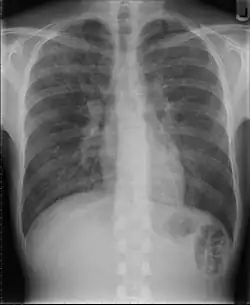

Röntgen

Beim Verdacht auf eine Pneumonie werden in der Regel zwei Röntgenbilder der Lunge angefertigt. Im Röntgenbild stellen sich schlecht belüftete Areale hell dar. Diese können z. B. auf eine Lungenentzündung hindeuten. Diese Veränderung (Infiltrat) entsteht durch die Einwanderung von Leukozyten (Infiltration) und die entzündlich bedingte Schwellung. Sind die luftleitenden Teile der Lunge und die Lungenbläschen nicht betroffen – wie bei einer interstitiellen Pneumonie (Entzündung des Bindegewebes zwischen den Lungenbläschen) –, stellen sie sich im Röntgenbild dar (positives Bronchopneumogramm). Sind hingegen die Lungenbläschen in dem entzündeten Bereich nicht mehr zu sehen, deutet dies darauf hin, dass sich dort Flüssigkeit befindet und die Entzündung in den Lungenbläschen stattfindet wie z. B. bei einer Lobärpneumonie.

Einschränkend muss gesagt werden, dass der Röntgenbefund keine zuverlässigen Rückschlüsse auf das in Frage kommende Erregerspektrum erlaubt.